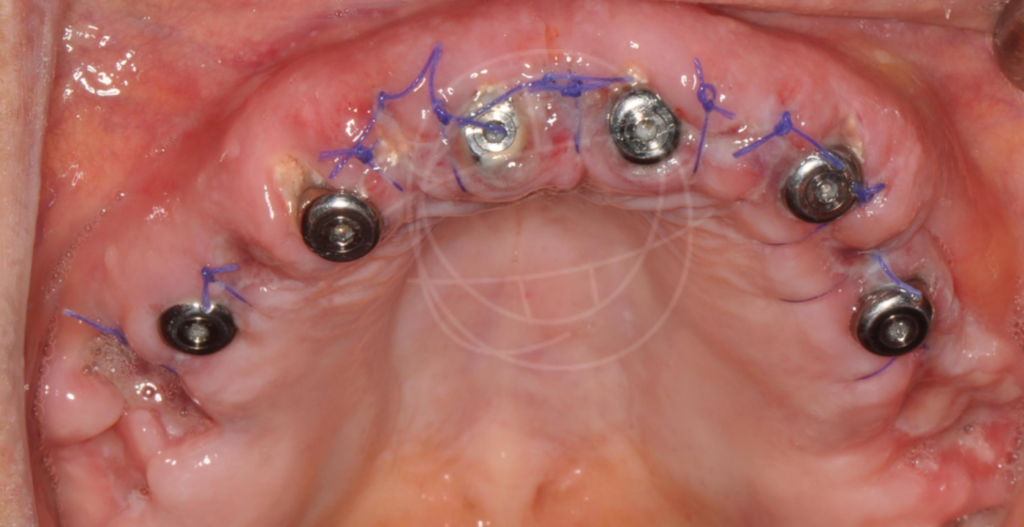

Ένα οδοντικό εμφύτευμα είναι μια «τεχνητή ρίζα» από βιοσυμβατό τιτάνιο, που τοποθετείται χειρουργικά στο οστό της γνάθου. Πάνω του στηρίζεται μια στεφάνη (το «τεχνητό δόντι»), η οποία μοιάζει και λειτουργεί όπως ένα φυσικό δόντι. Γι’ αυτό και συχνά τα εμφυτεύματα θα τα ακούσετε ως «βιδωτά» ή «φυτευτά» δόντια.

Η προσέγγιση που ακολουθούμε βασίζεται σε επιστημονικά πρωτόκολλα και εξατομικευμένο σχεδιασμό, ώστε κάθε ασθενής να έχει ένα φυσικό και μακροχρόνια επιτυχημένο αποτέλεσμα.

Τα οδοντικά εμφυτεύματα έχουν μεταμορφώσει τη σύγχρονη οδοντιατρική από την ανακάλυψη της οστεοενσωμάτωσης από τον Per-Ingvar Brånemark το 1952, της διαδικασίας όπου το τιτάνιο συντήκεται φυσικά με το οστό. Αυτή η ανακάλυψη οδήγησε στα πρώτα επιτυχημένα εμφυτεύματα τιτανίου το 1965, αποδεικνύοντας τη μακροπρόθεσμη σταθερότητα και ασφάλειά τους. Σήμερα, τα οστεοενσωματωμένα οδοντικά εμφυτεύματα τιτανίου αποτελούν μια αξιόπιστη, ευρέως χρησιμοποιούμενη λύση για την αποκατάσταση ελλειπουσών δοντιών και τη θεραπεία σύνθετων στοματικών παθήσεων.